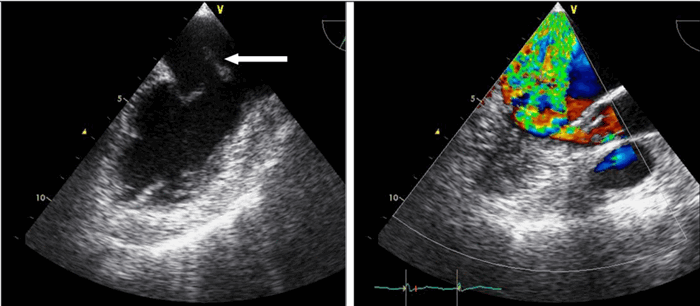

Постоянно-волновая допплер-эхокардиография

В отличие от импульсного исследования, где один и тот же кристаллический элемент и посылает, и принимает сигналы, при постоянно-волновом исследовании эти процессы разобщены: один кристаллический элемент посылает сигналы, другой принимает их. При исследовании в постоянно-волновом допплеровском режиме отраженный ультразвуковой сигнал принимается независимо от того, когда он был послан. Таким образом, исследуется кровоток вдоль всего ультразвукового луча (рис. 3.6). Главное достоинство постоянно-волнового допплеровского исследования состоит в том, что с его помощью может быть измерена любая скорость кровотока. На самом деле при постоянно-волновом исследовании ультразвуковые сигналы посылаются не непрерывно, а в виде отдельных импульсов. Изменение частоты повторения импульсов меняет масштаб допплеровского спектра. Частота повторения импульсов при постоянно-волновом исследовании, однако, ограничена только техническими средствами, но не пределом Найквиста. Современные эхокардиографы в принципе позволяют измерять скорости кровотока, достигающие 12 м/с, что выходит далеко за пределы возможного (скорость 12 м/с соответствует разнице давлений, превышающей 500 мм рт. ст.), так что с помощью постоянно-волновой допплер-эхокардиографии можно измерять любую скорость кровотока.

Рисунок 3.6. Пример исследования аортального кровотока в постоянно-волновом допплеровском режиме при аортальном пороке сердца. Исследуется кровоток вдоль всего ультразвукового луча. На допплеровском спектре регистрируется систолический поток через стенозированный аортальный клапан (AS) и диастолический поток аортальной регургитации (AI). Максимальная скорость (Vmax) стенотической струи составляет 4,1 м/с. По упрощенному уравнению Бернулли рассчитан максимальный градиент давления (Pmax) между левым желудочком и аортой, который оказался равным 67 мм рт. ст. CW Doppler Transducer — постоянно-волновой допплеровский датчик, LV — левый желудочек, LA — левое предсердие, Ao — восходящий отдел аорты, Velocity — скорость (м/с), Time — время (с). Judge K.W., Otto C.M. Doppler echocardiographic evaluation of aortic stenosis, in: Doppler Echocardiography, ed. Schiller N.B., Cardiology Clinics, 8 (2), 1990.

Главный недостаток постоянно-волнового допплеровского исследования — невозможность точной локализации исследуемого кровотока. Следовательно, импульсное и постоянно-волновое исследования дополняют друг друга: при импульсном исследовании выявляется область патологического, ускоренного, кровотока, при постоянно-волновом исследовании измеряется его скорость. Постоянно-волновое исследование существенно облегчается, если ультразвуковой луч направляется под контролем одновременно выполняемого двумерного исследования. Современные эхокардиографы позволяют проводить двумерную эхокардиографию и все виды допплеровских исследований с помощью одного датчика. «Замороженное» двумерное изображение позволяет контролировать положение ультразвукового луча и контрольного объема.

В большинстве современных эхокардиографов предусмотрена возможность трехмерной фокусировки ультразвукового луча при постоянно-волновом допплеровском исследовании: это увеличивает чувствительность метода. Кроме того, современные эхокардиографы оснащены датчиком, предназначенным исключительно для постоянно-волнового исследования. Небольшая площадь поверхности этого датчика позволяет точнее направлять ультразвуковой луч при ограниченном эхокардиографическом «окне», например, при исследовании из супрастернального или правого парастернального доступа.